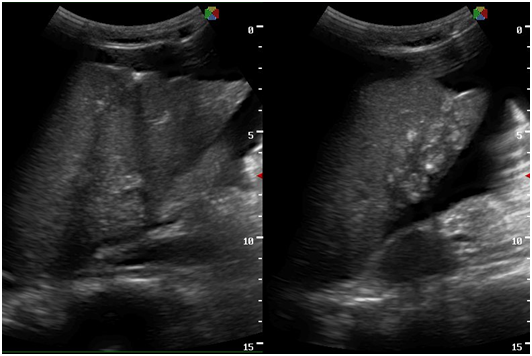

With the four‒month history of rapid abdominal enlargement and significant weight loss, the admitting impression was that of an ovarian new growth probably malignant. However, ultrasound showed only a left adnexal mass described as irregular tubular hyperechoic structure with scattered echogenic stipplings within, densely adherent to the postero‒lateral wall of the uterus, adjacent bowel loops and pelvic sidewalls, while the right ovary appeared grossly normal. Incidentally, there were multiple echogenic foci seen at inferior lobe and parenchyma of the liver, and massive anechoic free fluid was seen in the abdominopelvic cavity. A chest radiograph was also done, which showed pleural effusion on the right; findings suggestive of pulmonary tuberculosis, minimal disease. Work up for tuberculosis was done (Figures 2‒10).

Figure 5 Transabdominal view showing massive anechoic free fluid in the abdominopelvic cavity (ascites) and pallisading bowels.

Figure 6 There are multiple echogenic foci seen at the inferior lobe and parenchyma of the liver.

Figure 7 There is a thin midline echogenicity visualized (anteroposterior view), measuring 0.3 cm suggestive of the endometrial lining.

Figure 8 The surrounding myometrium (transverse view) which is hypoechoic, irregular, with scalloping at the periphery with a mixed hyperechoic and echogenic echopattern giving it a marblelized appearance, which may be a unique variation of the usual “moth‒eaten” appearance.

Figure 9 Normal right ovary.

Figure 10 At the left adnexal area is an irregular tubular hyperechoic structure with scattered echogenic stipplings within.

Tuberculous peritonitis is a variant of genital tract tuberculosis. Fallopian tube/uterine disease and tuberculous peritonitis can and does coexist in up to 50% of the cases.22 Tuberculosis is primarily an infection of the respiratory tract. Female genital tuberculosis can develop from a pulmonary nidus of infection or by hematogenous dissemination of organisms and their subsequent localization within the fallopian tube. When the gastrointestinal tract is the portal of infection, involvement of the ileocecal region permits lymphatic spread–primarily to the right fallopian tube.22 The sono graphic findings of this patient described a 5.3x4.6x3.8 cm tubular adnexal mass with scattered echogenic stipplings within, which probably represented tuberculous salpingitis. Myometrial involvement in this patient appeared as irregular scalloping at the periphery of the surrounding hypoechoic myometrium, giving it a marblelized appearance. Dissemination of disease from the fallopian tube occurs by continuous spread to potentially involve the ovary and retrograde into the uterus. Uterine extension involves primarily the endometrium with, at maximum, a 20% incidence of myometrial involvement.22